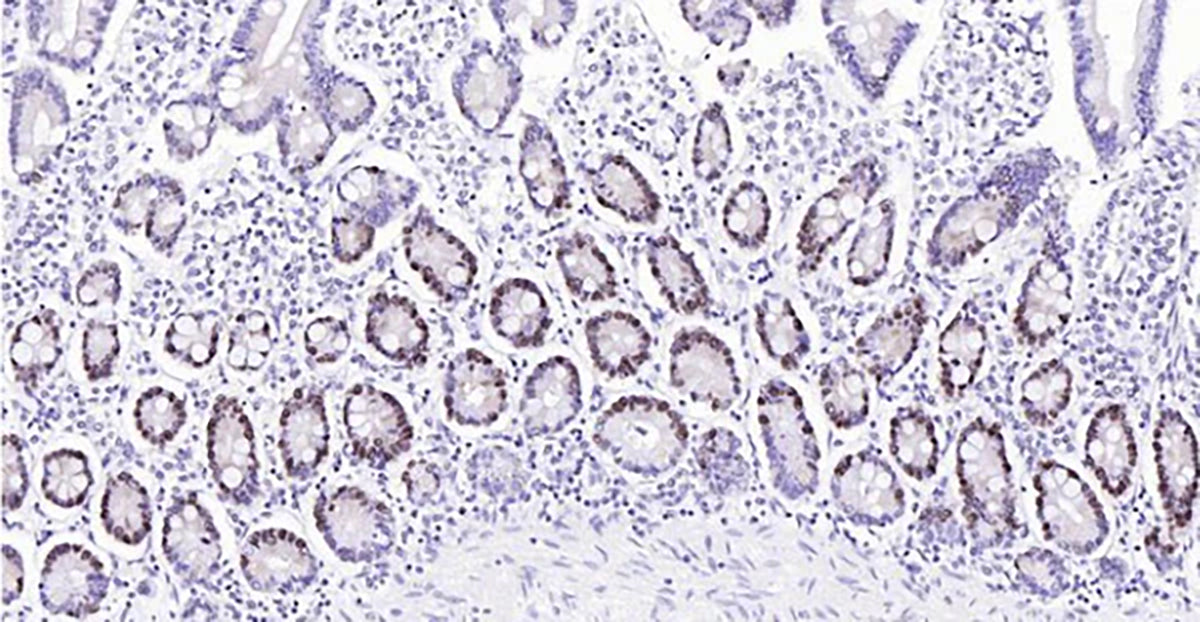

HRP Polymer Ready-To-Use Kits

The provided HRP polymer conjugated secondary antibody significantly address the limitations commonly experienced with traditional immunohistochemistry (IHC) methods, such as poor or inconsistent antigen staining when identifying low-abundance antigens or in situations of suboptimal antibody-antigen binding.

By utilizing an HRP polymer conjugate, the sensitivity of detection is dramatically increased and the process is simplified.Moreover, the HRP polymer-based amplification method reduces the amount of primary antibody needed and shortens the secondary antibodies’ incubation period.

Perfect for quickly and conveniently obtaining high-quality IHC data. These kits contain all the needed reagents, primary and secondary antibodies, AND a positive control slide to confirm your staining.